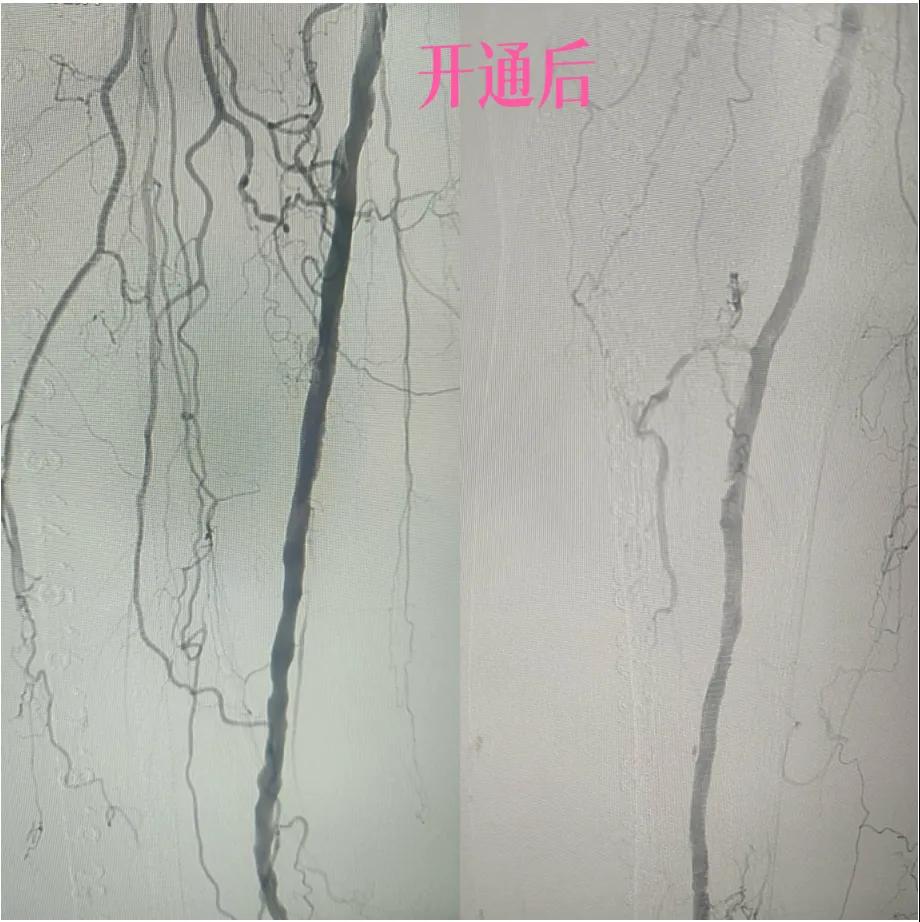

近日,漯河市中醫(yī)院外二科血管外科介入團(tuán)隊利用微創(chuàng)介入技術(shù)成功保住一患者患肢。

據(jù)悉,患者以“右足足趾疼痛伴第三足趾壞疽4月余”為主訴來院就診,查體患者右足第三趾末端呈壞疽狀,已結(jié)痂,足趾根部及足背部紅胖、壓痛,右側(cè)足背動脈,脛后動脈搏動未觸及,下肢深靜脈血管彩超:雙側(cè)下肢深動脈粥樣斑塊形成,右側(cè)腘動脈流速減低,右側(cè)脛后動脈及足背動脈不顯示(閉塞?)

為了挽救患者的患肢,避免截肢,外二科血管外科介入團(tuán)隊經(jīng)過縝密的術(shù)前討論和評估,決定采用目前微創(chuàng)介入技術(shù)——下肢動脈藥涂球囊擴(kuò)張成形術(shù)(DCB)。

2.  “探路”與“疏通”:在先進(jìn)的DSA(數(shù)字減影血管造影)設(shè)備實(shí)時引導(dǎo)下,猶如擁有了“透視眼”,導(dǎo)管導(dǎo)絲巧妙穿越病變血管的狹窄、閉塞段。這需要極高的技巧和對血管解剖的深刻理解。

3.  “球囊發(fā)力”:到達(dá)目標(biāo)閉塞段后,將未充氣的球囊導(dǎo)管送至病變部位。隨后,精準(zhǔn)控制壓力,使球囊緩慢充盈擴(kuò)張,如同在血管內(nèi)部進(jìn)行精細(xì)的“拓荒”,將堵塞的斑塊擠壓、塑形,撐開狹窄的血管腔。

4.  即刻“見證”:再次造影顯示,原本狹窄閉塞的血管段血流恢復(fù)通暢!足部遠(yuǎn)端血管顯影較前明顯改善。手術(shù)過程順利,患者靜息痛較前明顯改善。